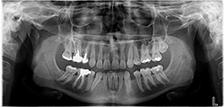

科技领先,全功能CCD传感器,直接数字化成像

采用世界领先科技全功能CCD传感器,连接电脑直接成像,方便快捷

扫描时间短暂,拍摄的图像清晰

采用意大利原装进口机头、传感器与电控板,性能稳定,扫描时间短暂,图像清晰